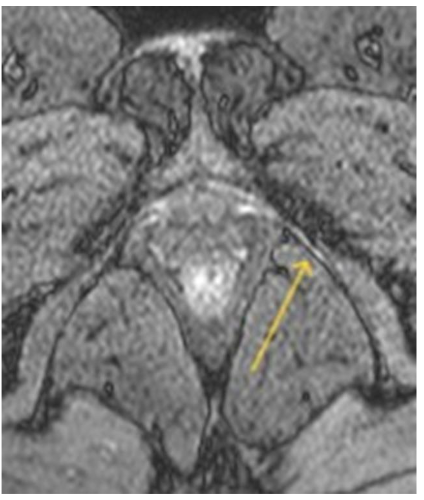

A 0-3 point brightness visual scale (B-scale) was developed to grade pudendal nerve injury within Alcock’s canal by comparing its signal intensity on axial DP SPAIR double IR BB images to that of static intravescical fluid, where 0 = no hyperintensity (no injury); 1 = barely visible hyperintensity (mild injury); 2 = clearly visible hyperintensity (moderate injury); and 3 = maximum intensity, equal to that of tissues containing static fluid (severe injury).

MR FINDINGS

MR neurography was successfully performed in all 100 patients using the described 1.5T protocol. Image quality was deemed sufficient for diagnostic interpretation in 96% of cases by both Observer 1 and Observer 2. The pudendal nerve was consistently visualized in cases of damage, appearing as a hyperintense linear structure on DP SPAIR BB images along its course from the sacral foramina to its terminal branches within Alcock’s canal, without the need for contrast administration.

Signal abnormalities were most frequently observed at the level of the ischial spine and Alcock’s canal, consistent with known anatomical entrapment sites. Additional findings included architectural distortion, nerve thickening, and obliteration of perineural fat planes features indicative of chronic neuropathic changes.

To our knowledge, this is the first report describing a method to isolate and visualize the pudendal nerve akin to a vessel in a subtraction angiogram using conventional 1.5T equipment and without contrast agents. This is achieved through a specific pulse sequence that simultaneously suppresses flow and fat signals, enabling clear differentiation between vessels and nerves within Alcock’s canal, where they course in close proximity. The rationale for selecting the Black Blood (BB) pulse sequence lies in its ability to suppress signal from flowing blood in the pudendal vessels, thereby enhancing the visibility of stationary fluid within the damaged nerve. This requires synchronization of image acquisition with the cardiac cycle (cardiac gating) using ECG monitoring to capture data at consistent points between successive R-waves. Additionally, a double inversion recovery (DIR) 180-degree preparation pulse nulls the signal from flowing blood as it enters the region of interest, while also suppressing fat signal and preserving the visibility of stationary structures. Consequently, any signal increase within Alcock’s canal can be confidently attributed to the pudendal nerve.